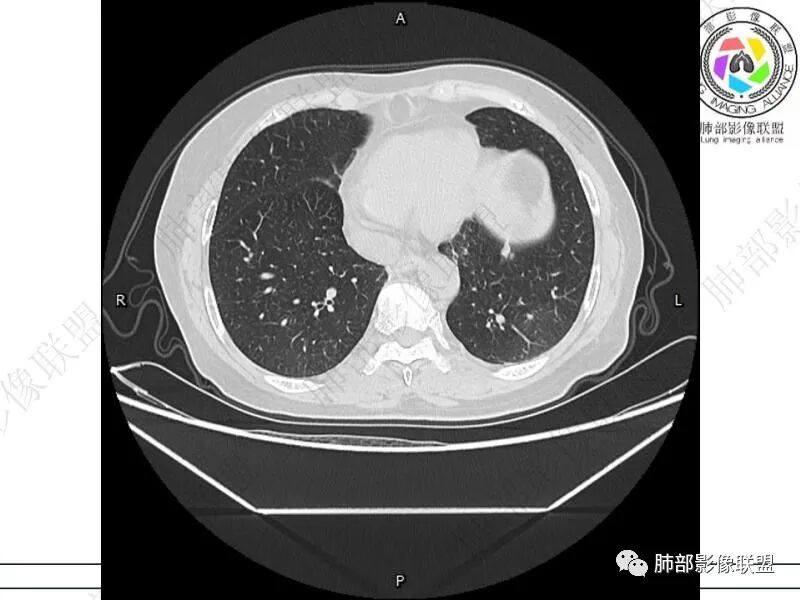

丽:双肺下叶胸膜下多发片状高密度影,边缘模糊不清,内可见支气管穿行,病变长轴平行于胸膜,考虑感染性病变,隐球菌

媛:肠癌术后,免疫力低下。两肺胸膜下结节及实变影,实变影长轴平行于胸膜,密度均匀,边界偏清,周围有晕征,短期复查进展,虽隐球菌荚膜抗原检测阴性,还是考虑隐球菌,鉴别OP

谢加平:结肠癌术后史,两肺胸膜下多发结节及斑块实变病灶,实边边界平直征(亚急性和慢性病变过程),双肺下叶后基底段胸膜下为甚,与胸膜平行特点,见支气管充气征,边缘模糊的GG0,首诊2022年11月18日肺部CT,与治疗11月28日对比,病灶未吸收,双肺下叶胸膜下病灶有侧向融合特点,综合分析符合炎性肉芽肿,隐球菌感染。

老年女性,结肠癌术后。两下肺胸膜下为主片状实变,右下肺短期复查融合且病灶长轴平行于胸膜,实变内可见支气管充气征,边缘磨玻璃晕,另两肺内胸膜下散在数枚小结节状、楔形实性灶。考虑感染性病变,隐球菌可能,鉴别肺转移。

2.影像特征:双肺胸膜下多发实性结节、磨玻璃影及实变影,胸膜下优势分布、晕征、胸膜下脂肪间隙存在,部分病灶边界平直征,有侧向融合趋势。